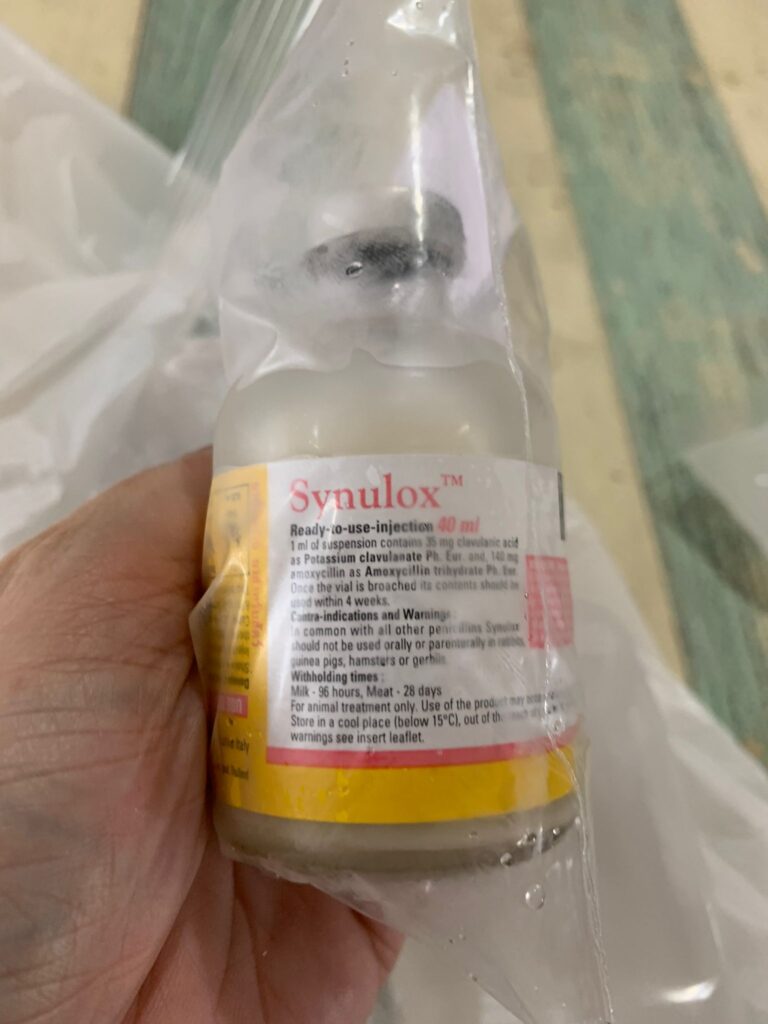

Morning; both eyes discharge look bad, clean up and put banocin on his ear. Will Subcut him and give Clav jab and bupre n put on new f patch for him

Morning: f patch intact. Apply banocin powder on ear. Still look got blood clog, didn’t bleed further. Given 5th and last Clav jab.

2pm+: checked on him, is right ear got one line, quite deep, bleeding but alr stop. Will give him 5 days ab 0.2ml clav to play safe. Given Subcut n bupre 0.2ml. 3.99kg – gain 80g in a month. Got walk about to eat

HCT 29.5%, dr nally say she don’t like her EOS 3.24, but it’s a gone down figure cos March he had fenbendazole alr. Will tell them deworm him today. Alt 177 – continue ornipural. GGT 6, restart ursofalk 65mg. 15mg/kg in short. add on Clav 14 days, 0.22ml and anti histamine jabs (expire dec 23) – price $188 don’t make sense so didn’t buy.

Subcut w B12 b com, Clav, day 03.

Clav day 06. did sneezing seem better? But I open windows now more often. Waste aircon.

Day 08 on Clav. Maybe did help in nose.

Keep sneezing. W blood also. The wall also the carrier bag also. Can’t feel anything from the teeth side, cos both blood from both nostrils. So even take head X-ray can’t see the back from the nose, just whack Clav 10 days 0.25ml. See first.

Night: given him Clav 0.25ml and ornipiral. No more oral med.